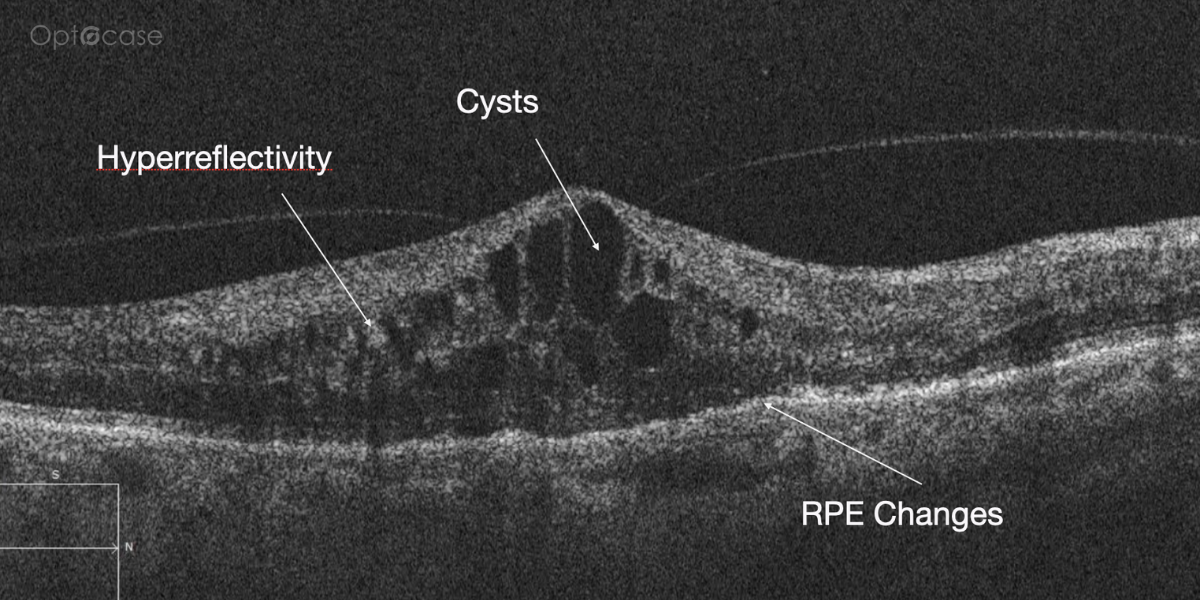

Here there is loss of the regular macular depression. There is a bright line present on the surface of the retina. In addition, there is separation of the retinal layers in the inner retina.

The patient was diagnosed with a schisis secondary to an epiretinal membrane. This complication is seen in over 50% of ERMs (video).

In any patient with intraretinal fluid consider the possibility of an epiretinal membrane causing a schisis.